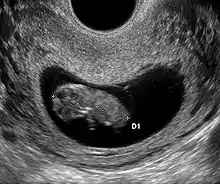

- Le premier signe échographique d'une grossesse est la visualisation d'un sac ovulaire. Il est visible entre 4 semaines et 1 jour et 4 semaines et 3 jours; Il mesure alors 2 à 3 mm. L'utilisation de la voie endovaginale est souvent nécessaire pour le voir. Le sac ovulaire a l'aspect d'une petite tache noire, excentrée par rapport à la cavité utérine, correspondant à la cavité chorionique entourée d'une couronne d'échogénéicité forte : le trophoblaste.

- À cinq semaines, le sac ovulaire mesure 5 mm. Il est quasiment toujours visible lors de l'échographie par voie abdominale. Il est parfois difficile d'affirmer la localisation intra-utérine de la grossesse en raison de l'aspect de pseudo-sac gestationnel décrit au cours des grossesses extra-utérines. Seuls deux signes sont pathognomoniques de la grossesse intra-utérine

- L'aspect en double cercle du sac (double decidual sac sign) correspondant une couronne hyper-échogène interne en rapport avec la trophoblaste et une couronne hypo-échogène externe en rapport avec la transformation gravidique de l'endomètre

- La visualisation de la vésicule vitelline qui affirme définitivement le caractère ovulaire de l'image échographique.

- La visualisation de la vésicule vitelline est un élément essentiel pour affirmer le caractère ovulaire de l'image et l'évolutivité de la grossesse. Embryologiquement, la vésicule vitelline visualisée correspond à la seconde vésicule vitelline. La vésicule vitelline est toujours visible à 5 semaines et 5 jours par voie endovaginale. Le sac ovulaire mesure en moyenne 8 mm. Par voie abdominale, elle est toujours visible à 7 semaines (le sac ovulaire mesure en moyenne 20 mm). Le diamètre de la vésicule vitelline augmente de 5 à 10 semaines pour atteindre 5 à 6 mm.